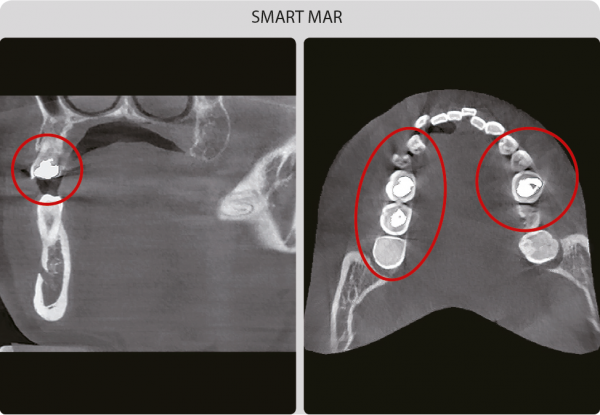

SMART MAR – алгоритм уменьшения появления артефактов от металлов при томографии

Свечение металла значительно снижает диагностическую ценность 3D исследований Технология SMART MAR обеспечивает минимальные потери качества изображения при наличии металла у пациента.